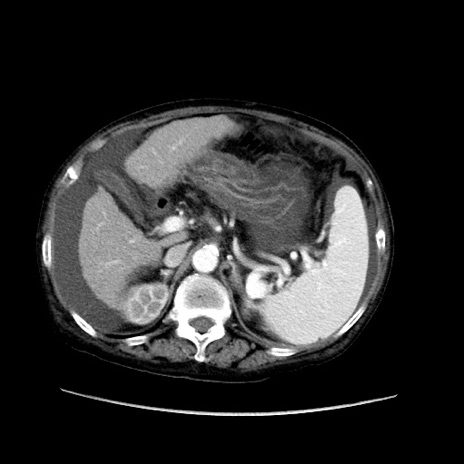

症例31(横断像)

【症例】80歳代 女性

【主訴】腹部膨満感

【現病歴】他院にて肝硬変にてフォロー中。1週間前から便秘、腹部膨満感、臍部腫瘤あり受診となる。

【既往歴】肝硬変

【身体所見】腹部膨隆あり、皮膚変化なし、疼痛なし。

【データ】WBC 4600、CRP 0.25